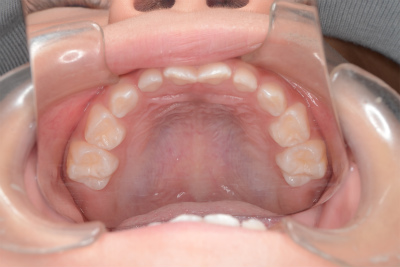

小学5年生

定期的に私の歯科医院に来てもらいフッ素を塗って歯の写真をとっていますが、今回も3人の歯にはムシ歯はありませんでした。